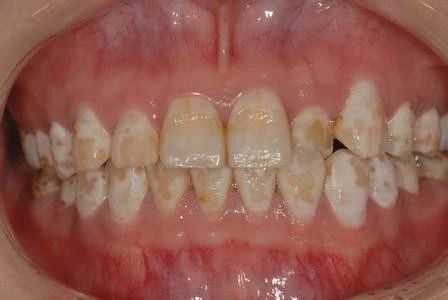

牙齿颜色为什么会发生变化?变化的原因又是什么?今天我们来简要的了解一下。

许多人误以为牙齿发黄仅仅是牙齿表面发生颜色变化,想象把表层磨掉,牙齿就能变白了。其实牙齿里面的颜色和外表并没有多大差异,牙齿表面颜色的变化,就是人体生理因素发生变化后对牙齿带来的影响和变化,而其中骨骼系统生理因素的变化,对牙齿颜色的影响是最直接,也是最大的。

比如人体的慢性氟中毒,氟主要侵害的就是骨骼系统,最后它能让人体的关节,脊骨慢慢变形,但它首先表现出现的症状,就是牙齿变黄、变黑、缺损和脱落。

又比如在一些特殊的地区因为水质的原因,造成生活在这一地区的人们出现了统一的受损标志——黄牙(氟斑牙),这些都是先因骨骼系统受到了轻微的侵害后,引起牙齿出现连锁反应,并导致牙齿中原有的某些重要元素流失了,最后引起牙表色泽上的变化。